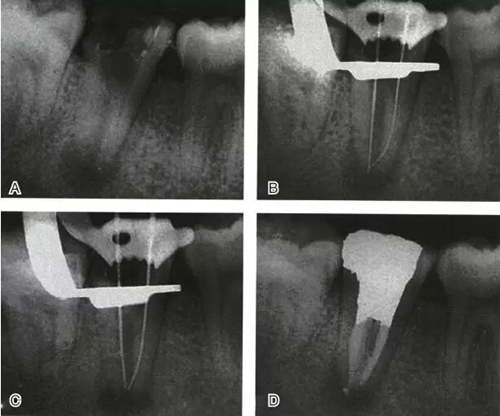

根管充填是C形根管治療成功與否的最重要因素。充填C形根管系統(tǒng)時,近舌及遠中根管可以進行常規(guī)充填。關(guān)于狹區(qū)的充填,更適合以熱牙膠垂直加壓充填,這種方法可使牙膠到達根管系統(tǒng)的每一死角(圖4~7)。

圖4 Ⅰ型C形根管治療典型病例一,A:初始片,B:初尖銼片,C:主尖銼片,D:充填片

圖5 Ⅰ型C形根管治療典型病例二,A:初始片,B:初尖銼片,C:主尖銼片,D:充填片